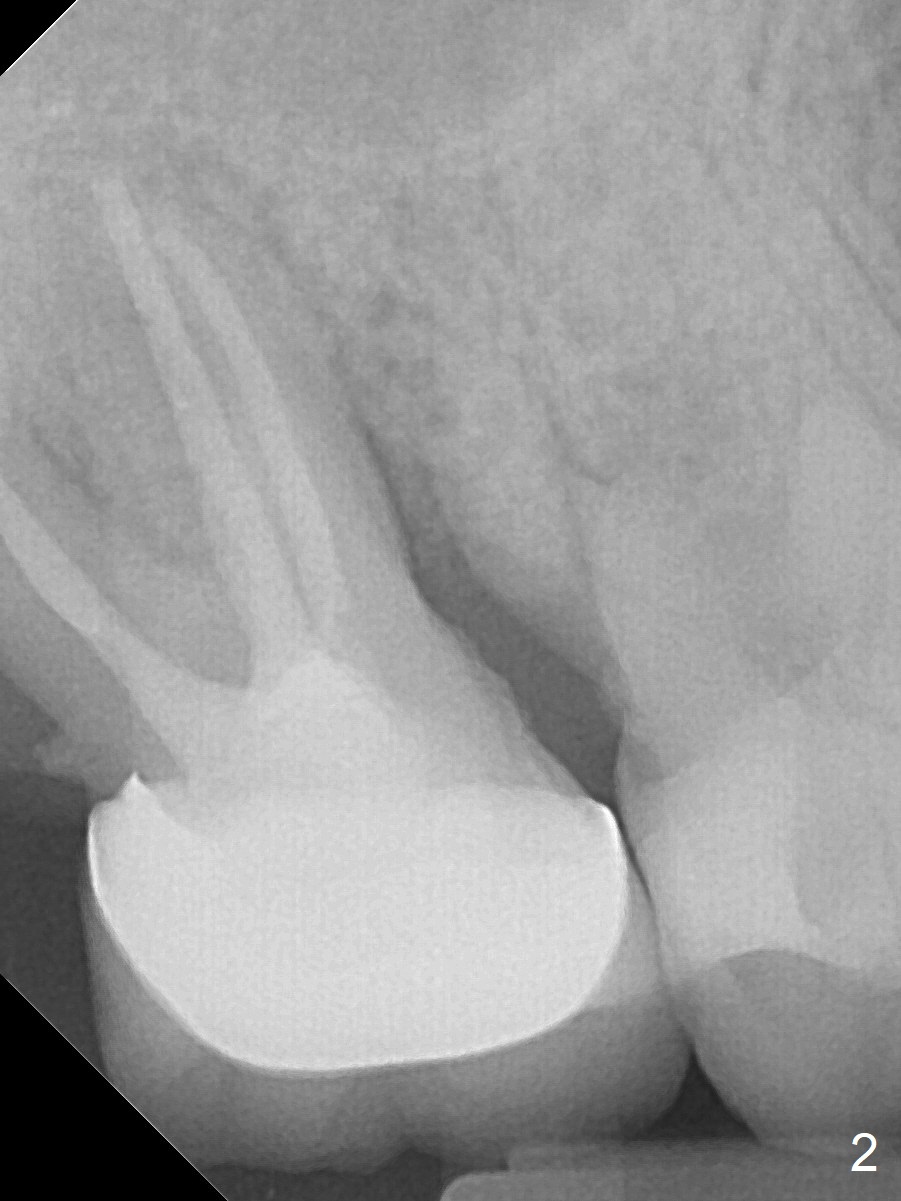

A 65-year-old man returned to finish LR and LL quadrant SRP a few weeks post SRP for UR quadrant and #2 extraction (Fig.1-2). He returns for UL SRP tomorrow ~ 3 months post extraction (Fig.4). Although the patient cannot remember whether socket preservation is done or not, there appears to be bone graft in the socket. The ridge is wide. It seems reasonable to expand and condense the socket using Magic Split and Expanders (flapless). If the patient cannot tolerate tapping, use DIO Bone Expanders. A 6.5x9 (3) mm Magicore will be placed (Fig.5,6).